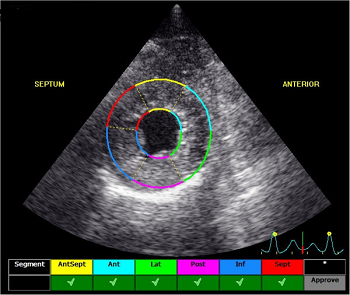

The echocardiograph examination shows the dimensions of the heart chambers, wall thickness and movement, valve movement and lesions, fractional shortening, among other characteristics. The echo screen shows the amount of wall contraction, which enables the operator to determine contractility, preload*, and afterload*. These factors are used to calculate "fractional shortening" (FS%) which is used as an indication of ventricular performance and of myocardial contractility.

See, also, this March 2017 article, in which the same investigators used 3-D echocardiography analysis on 113 dogs, including 13 cavaliers affected in varying stages of MVD. The 3-D echos enabled the investigators to compare the morphology of the mitral valves (MVs) of healthy dogs (none were CKCSs) and MVD-affected dogs. They report that the study demonstrated that the MVs of MVD-affected dogs differed from those of healthy dogs in several morphological aspects. In particular, the affected dogs had an increased sphericity and a decreased saddle shape of the MV annulus, as well as a decreased tenting height, area and volume. See Figure 1. The study also reportedly demonstrated significant differences in multiple 3-D echo MV measurements between dogs in varying stages (B1, B2, C) of MVD.